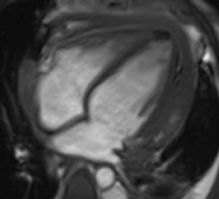

Diagnostic Techniques and Their Most Important Findings: Chest CT revealed bilateral small pleural effusions, significant pericardial effusion, and minimal ascites. Transthoracic echocardiogram showed moderate-to-large pericardial effusion without hemodynamic compromise. Cardiac Magnetic Resonance Imaging (CMR) demonstrated pericardial thickening, enhancement of the pericardial leaflets, and mild-to-moderate exudative pericardial effusion suggestive of pericarditis. Due to high suspicion of tuberculous etiology, pericardiocentesis followed by surgical pericardiotomy was performed. Although pericardial fluid analysis was nonspecific and negative for acid-fast bacilli, pericardial biopsy confirmed granulomas with caseous necrosis. Anti-tuberculosis therapy was started with subsequent clinical improvement.

Learning Points from this Case: Concato’s polyserositis is a rare but severe manifestation of extrapulmonary tuberculosis, particularly in children. Diagnosis requires a high index of suspicion, especially in endemic areas, and imaging plays a central role. In this case, CMR findings were instrumental in guiding invasive diagnostic procedures. While pericardial fluid analysis may be inconclusive, histopathological examination remains essential for definitive diagnosis. Early recognition and appropriate treatment of tuberculous pericarditis can prevent complications such as constrictive pericarditis and improve outcomes.

Pericardial effusion

Diagnostic Techniques and Their Most Important Findings: Chest CT revealed bilateral small pleural effusions, significant pericardial effusion, and minimal ascites. Transthoracic echocardiogram showed moderate-to-large pericardial effusion without hemodynamic compromise. Cardiac Magnetic Resonance Imaging (CMR) demonstrated pericardial thickening, enhancement of the pericardial leaflets, and mild-to-moderate exudative pericardial effusion suggestive of pericarditis. Due to high suspicion of tuberculous etiology, pericardiocentesis followed by surgical pericardiotomy was performed. Although pericardial fluid analysis was nonspecific and negative for acid-fast bacilli, pericardial biopsy confirmed granulomas with caseous necrosis. Anti-tuberculosis therapy was started with subsequent clinical improvement.

Learning Points from this Case: Concato’s polyserositis is a rare but severe manifestation of extrapulmonary tuberculosis, particularly in children. Diagnosis requires a high index of suspicion, especially in endemic areas, and imaging plays a central role. In this case, CMR findings were instrumental in guiding invasive diagnostic procedures. While pericardial fluid analysis may be inconclusive, histopathological examination remains essential for definitive diagnosis. Early recognition and appropriate treatment of tuberculous pericarditis can prevent complications such as constrictive pericarditis and improve outcomes.

Pericardial effusion